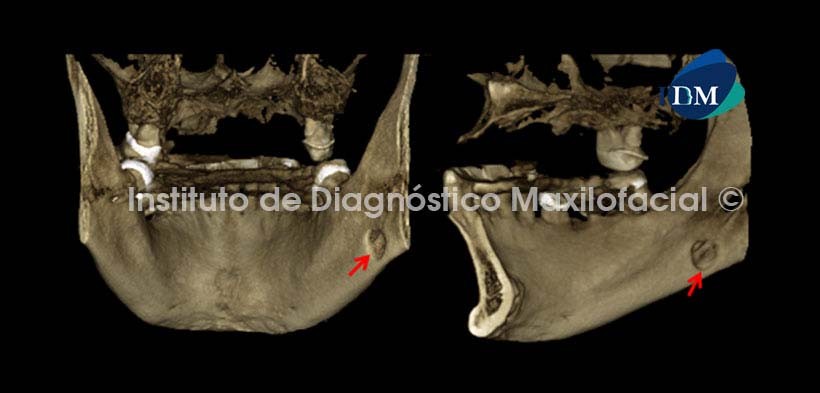

En las reconstrucciones tridimensionales se observa el defecto óseo desde una vista posterior e interna respectivamente.